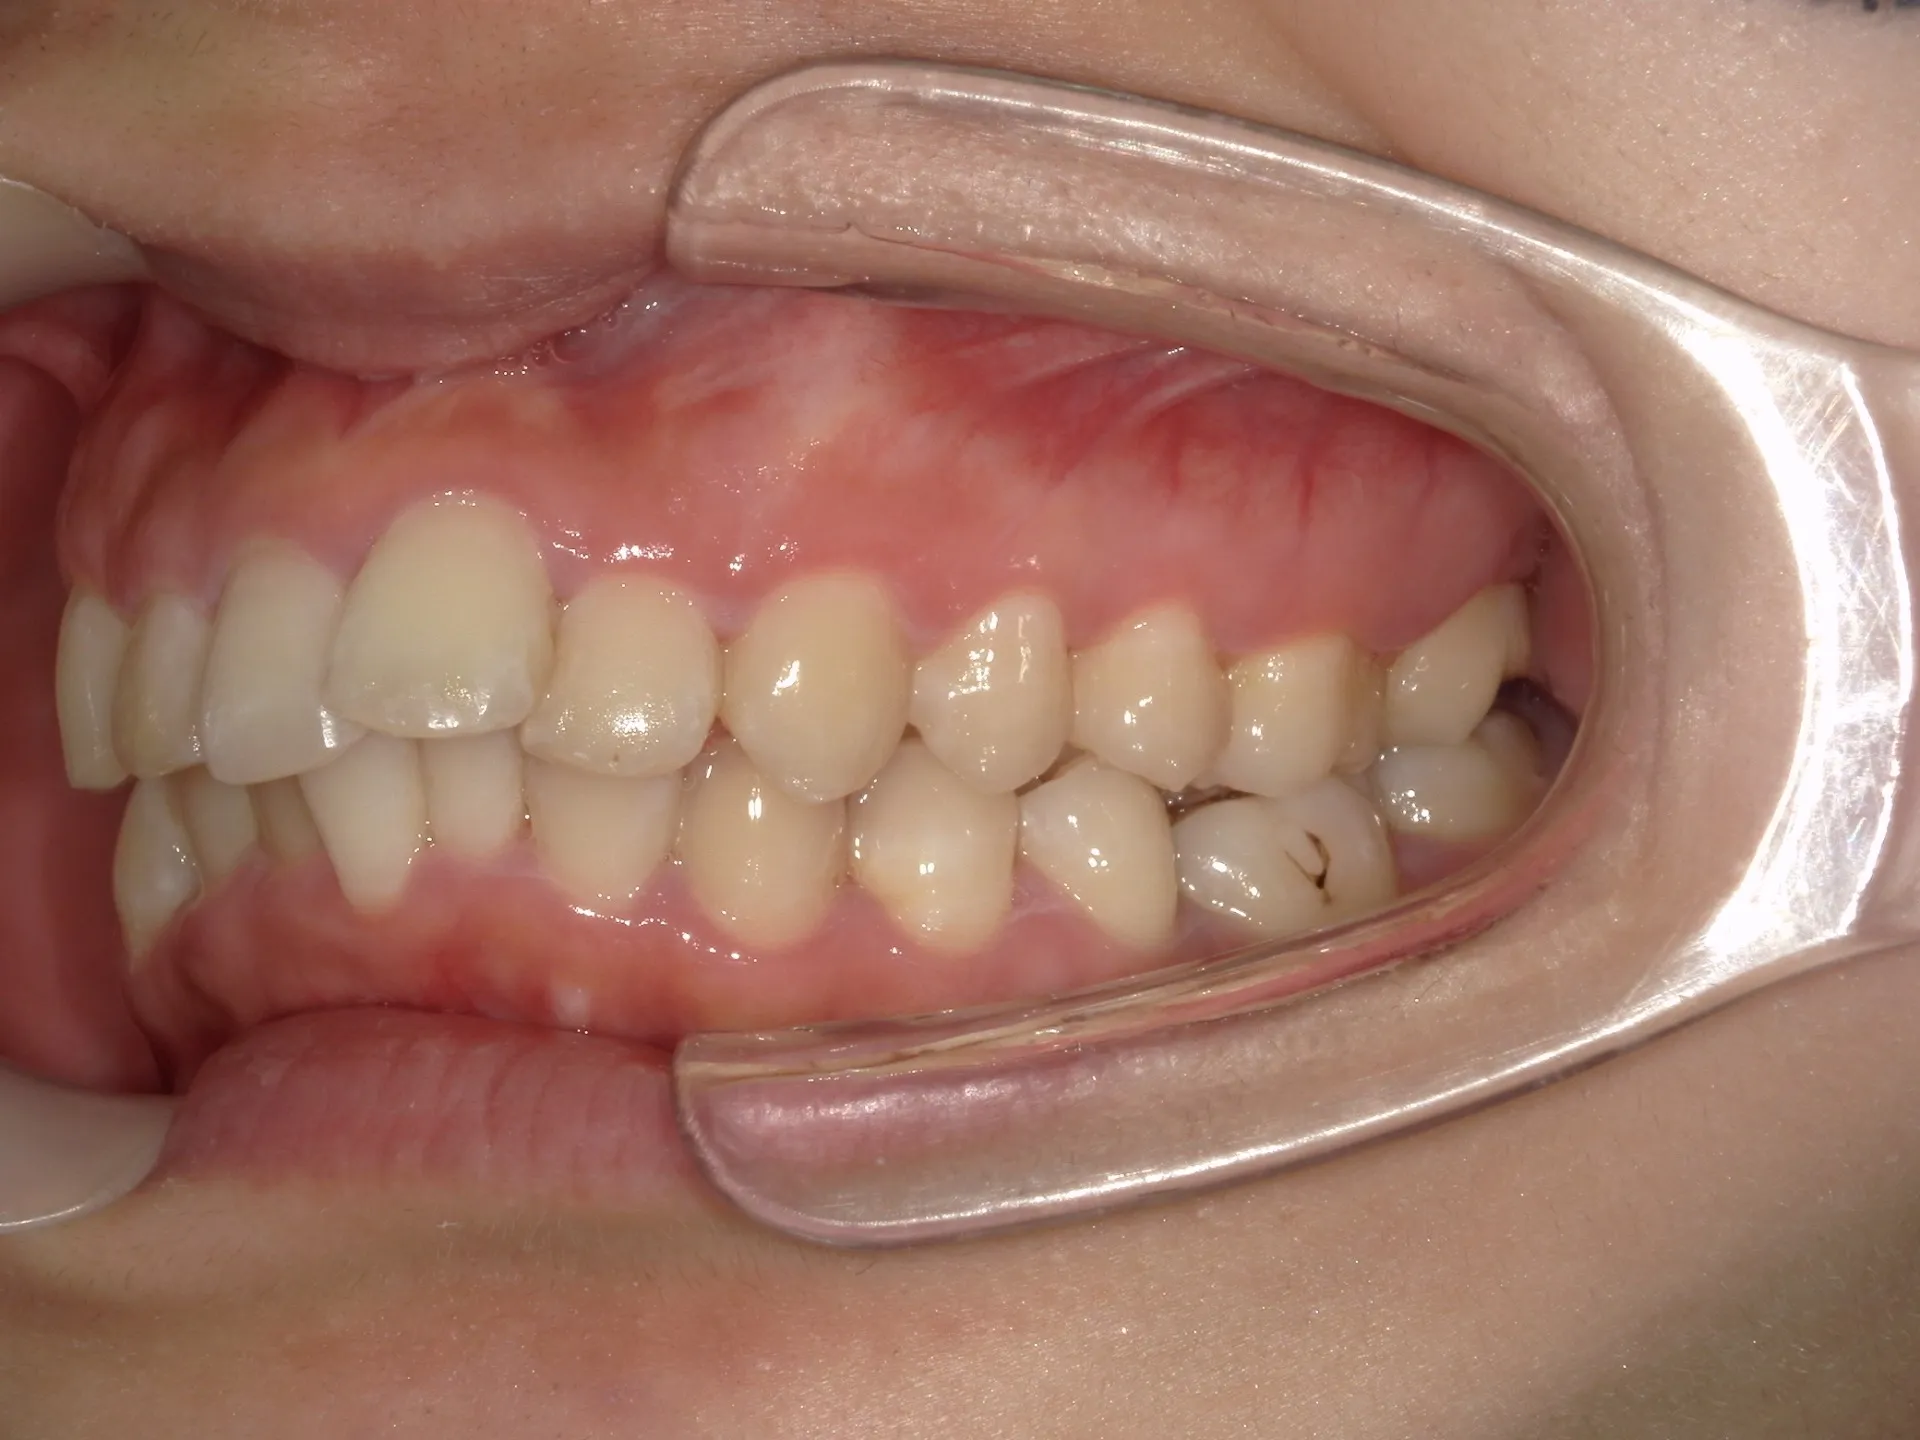

今回はマウスピース矯正(インビザライン)で前歯の出っ張りを治したケースをご紹介いたします。

マウスピース矯正で前歯の出っ歯感を抑えることが可能で、このケースでは上の歯のみ2本の抜歯を行っています。